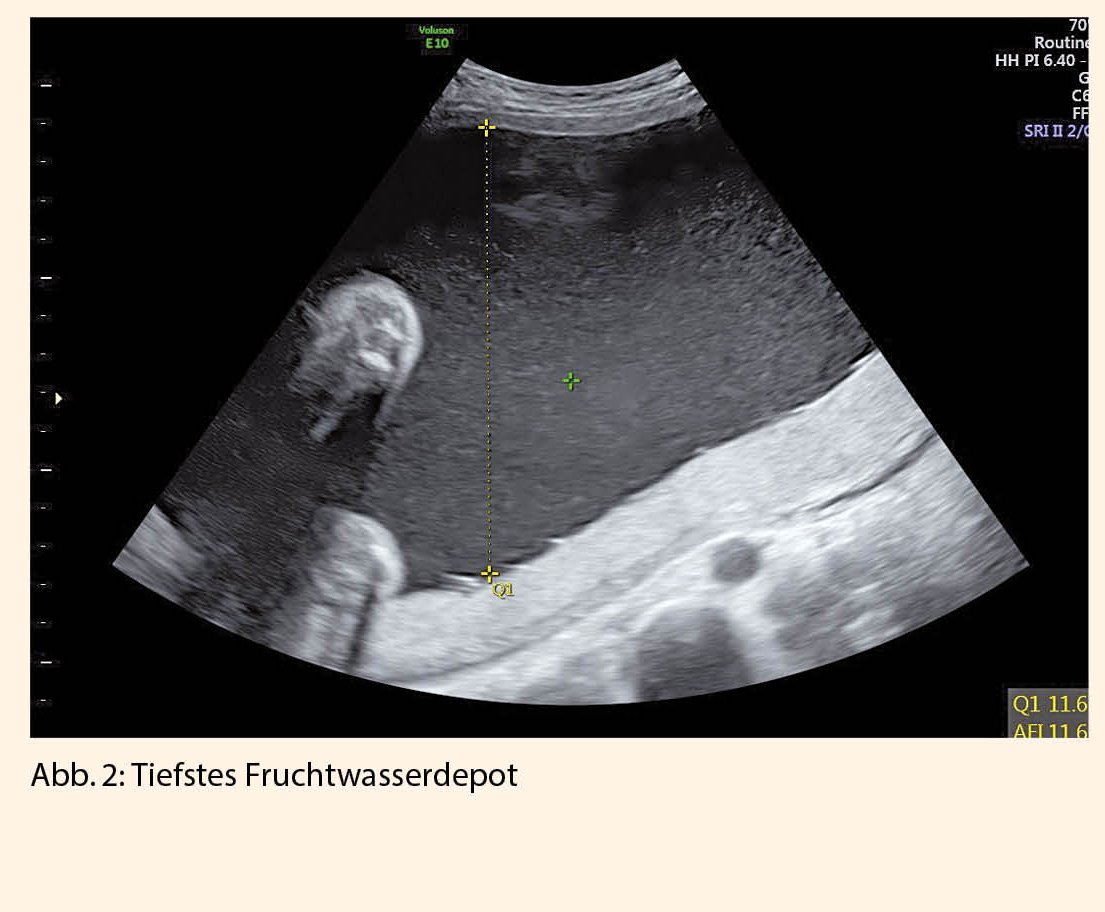

Die gängigsten Methoden zur Bestimmung der Fruchtwassermenge sind die 4 Quadranten-Messung ( Abb. 1) mit einem oberen Normwert von 25 einerseits und die Messung des tiefsten Fruchtwasserdepots (Abb. 2) mit dem jeweils grössten vertikalen Ausmass andererseits, wobei ein Wert über 8 einem Polyhydramnion entspricht. In einer Übersichtsarbeit, in der randomisierte Studien über den Vergleich zwischen Fruchtwasserindex und tiefstem Fruchtwasserdepot analysiert wurden, konnte gezeigt werden, dass die Messung des Fruchtwasserindex mehr vermeintliche Fälle mit einem Oligohydramnion identifizierte (1).

Dies hatte zur Folge, dass signifikant häufiger Interventionen wie Geburtseinleitung und Kaiserschnitt erfolgten, wodurch das fetale Outcome hierdurch allerdings nicht verbessert werden konnte.